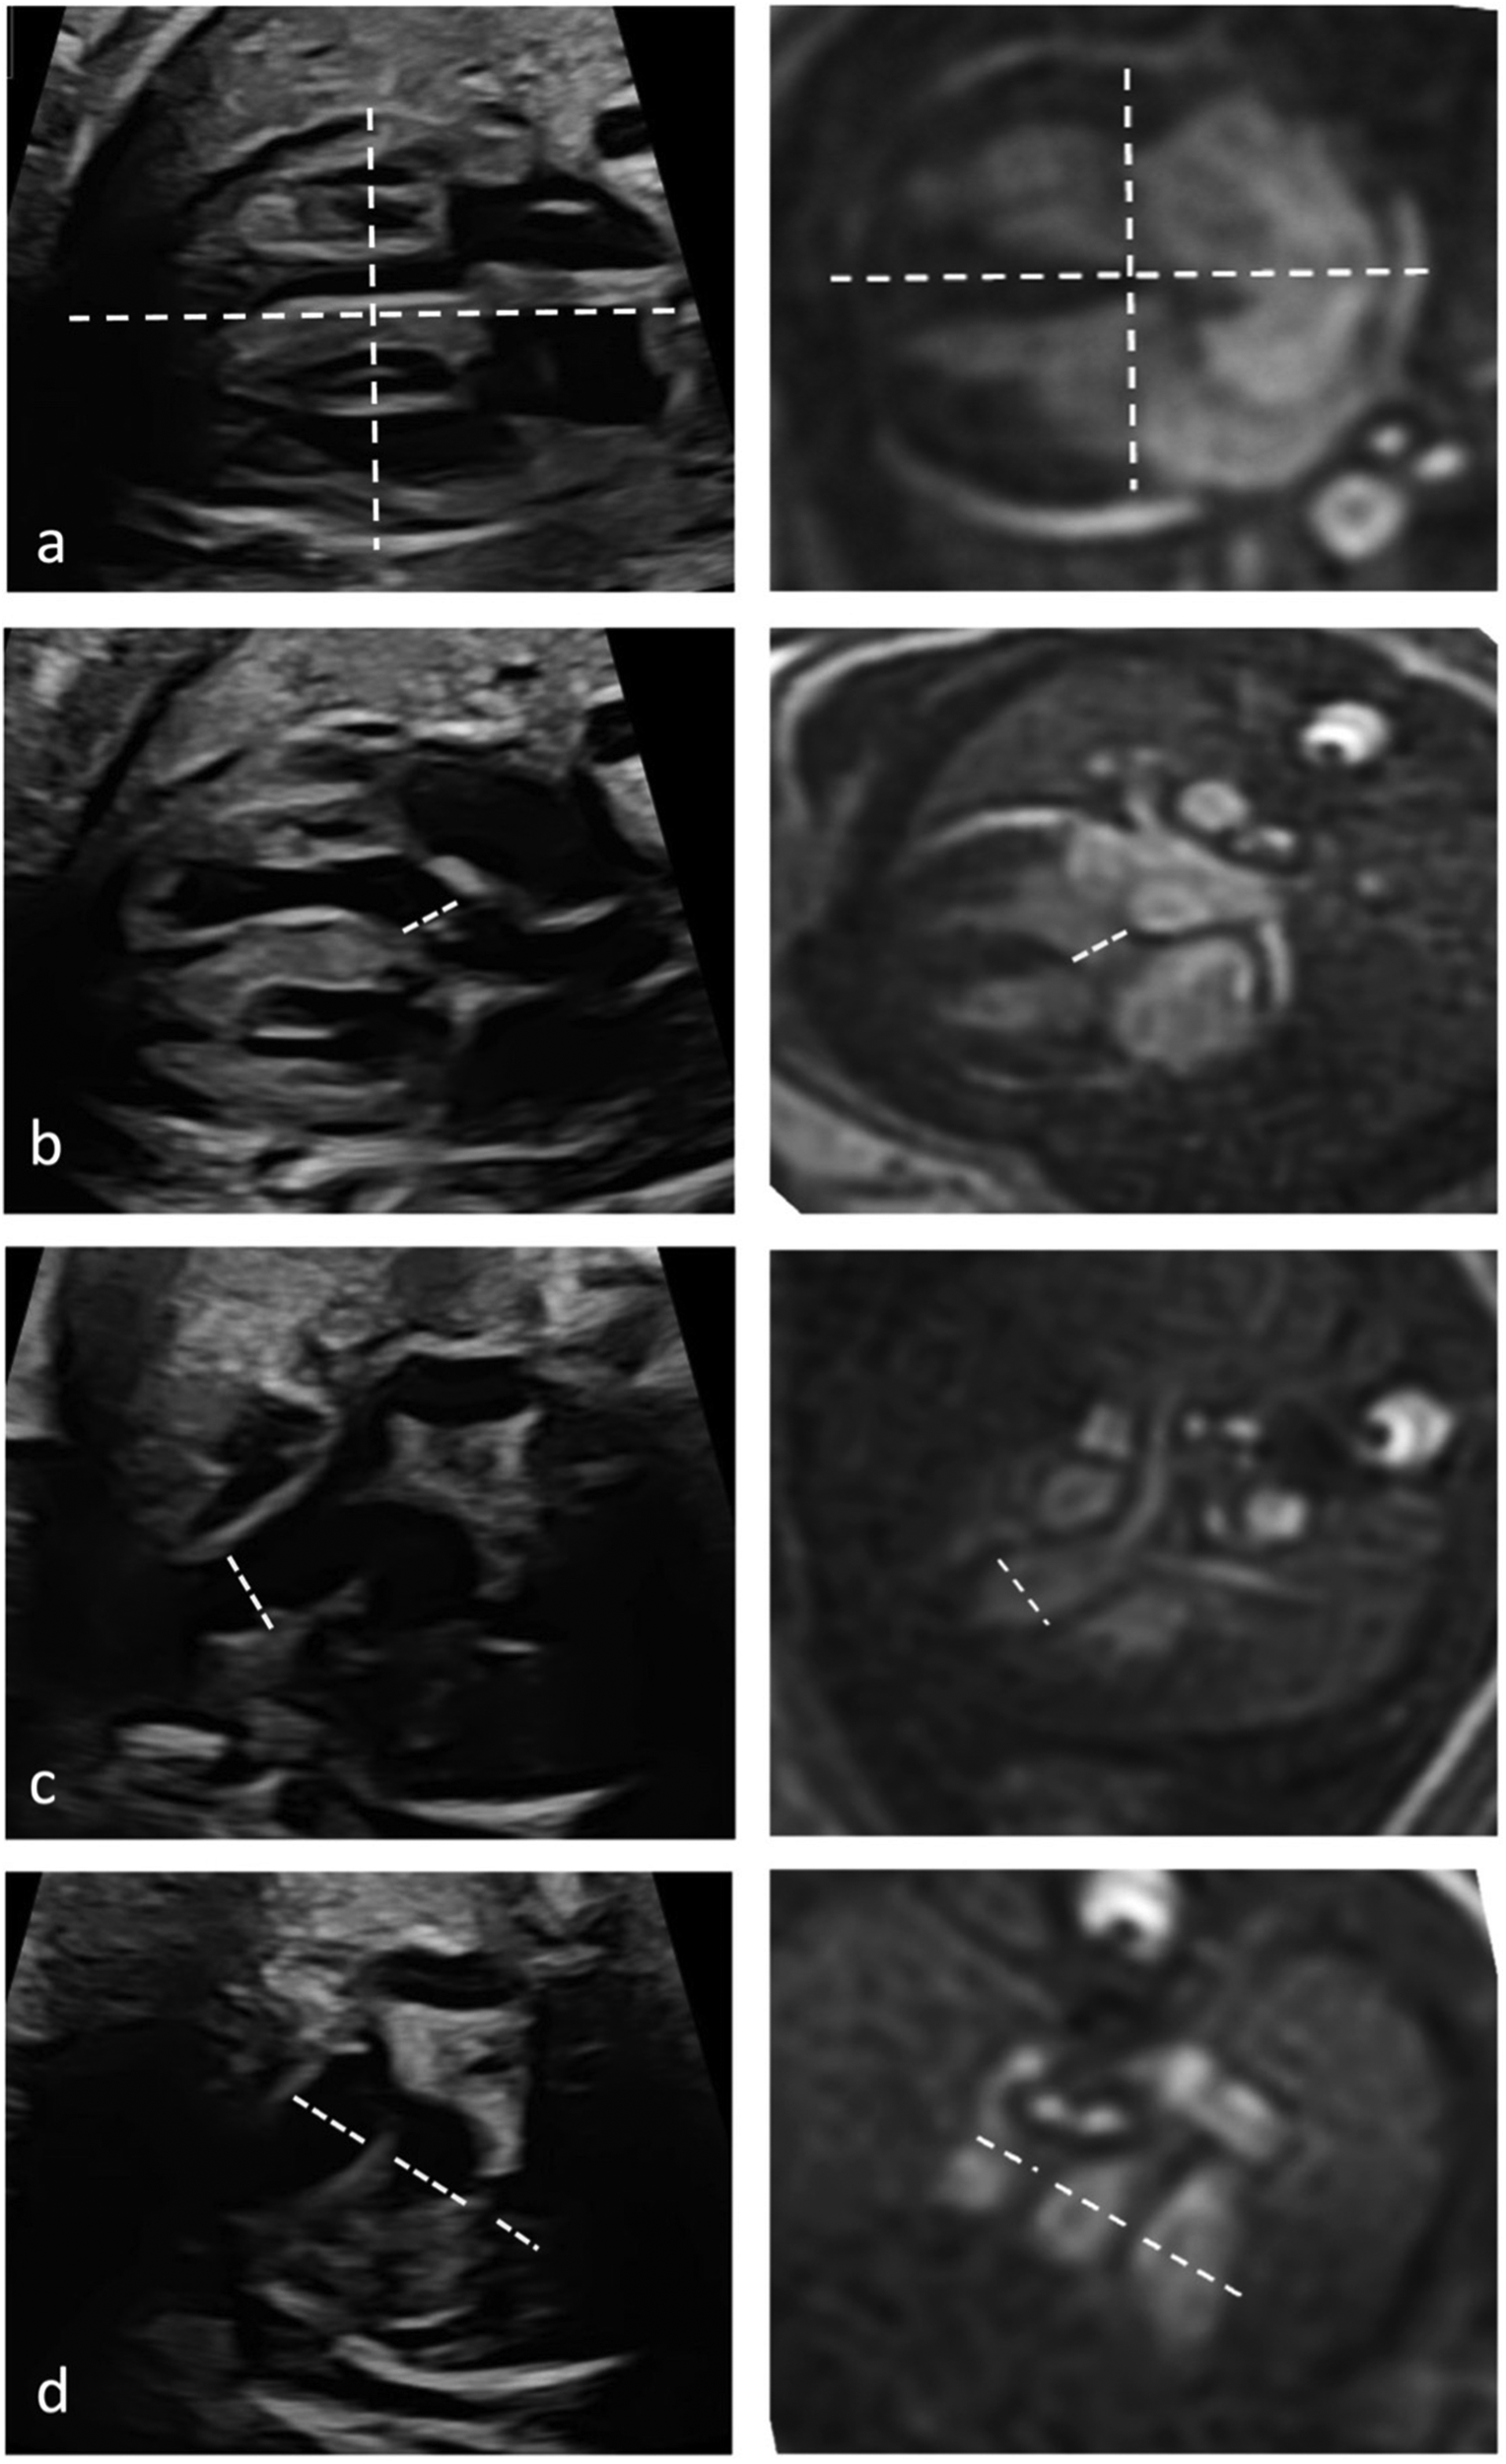

Quantitative evaluation of diameter measurements in the five axial views showed no differences between fetal cardiovascular MRI and fetal echocardiography (Table 3). Examples of measurements are provided in Figure 4.

Figure 4

Quantitative assessment of cardiac diameters. Diameter measurements in fetal cardiac five axial views in a healthy Fetus (35 + 1 weeks gestation) in fetal echocardiography (left column) and cardiac MRI (right column). Longitudinal and transverse cardiac diameter from 4-chmaber view (a), diameter of the LVOT (b), the RVOT diameter (c) and diameters of pulmonary artery, aorta, and superior vena cava from the three-vessel view (d).